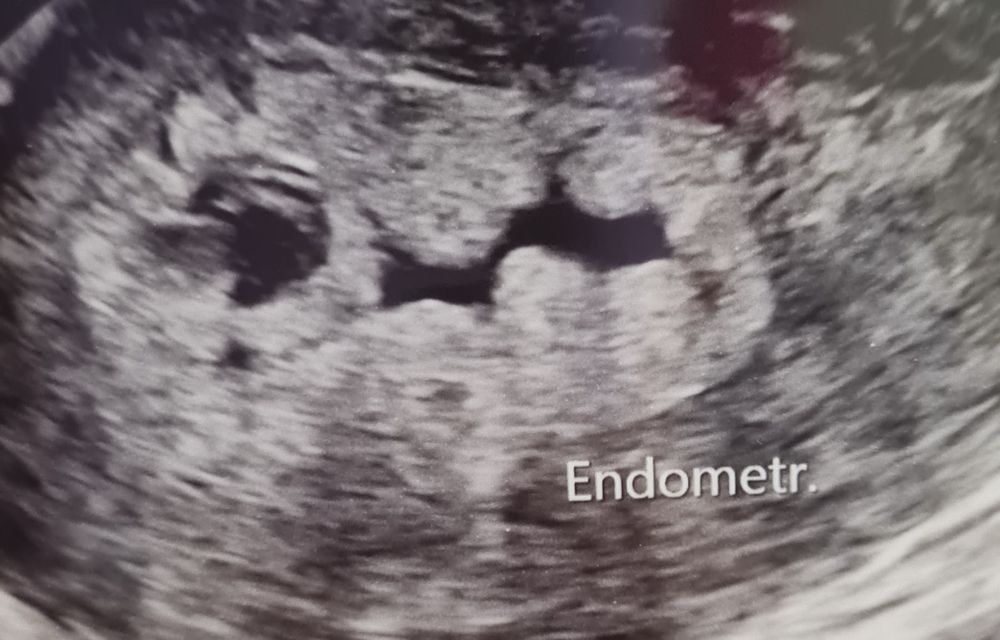

Но как гром среди ясного неба: ПЯ в матке не выявлено! Эндометрий увеличен до 27мм, с децидуальной реакцией пишут (на узи выглядит странно, волнами, с пространством). В передней стенке есть гипоэхогенное округлое включение диаметром 6,9мм. Но врач-узист говорит, что оно по структуре совсем не ПЯ, да и маленький для такого срока, как я поняла и сосудов вокруг нет. Больше нигде ни намёка на ПЯ! Желтое тело хорошее. Свободной жидкости не выявлено. Долго смотрела, по бокам и тп, трубы не визуализируются.

Прикрепляю фото странного эндометрия.